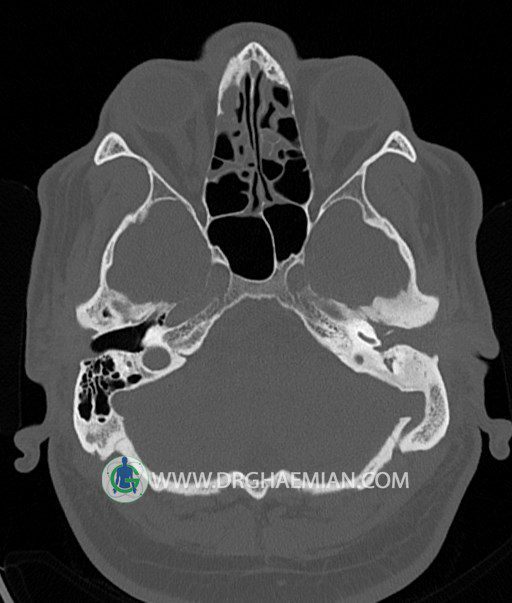

سی تی اسکن گوش داخلی به رادیولوژیست اجازه می دهد تا سطوح مختلف، یا اسلایس هایی از استخوان های که از جمجه به گوش می روند را از طریق امواج ایکس چرخشی مشاهده کند. در این کیس اودیت مدیا، ماستوئیدیت مزمن، اوتیت خارجی، انحراف سپتوم بینی، کونکا بولوزا و افزایش ضخامت سینوس ها مشاهده می شود.

در HRCT از استخوان تمپورال با مقاطع آگزيال ، ساژيتال و کرونال ظريف ( 0.6 mm ) :

– نماي کوکلهآي دو طرف با 2.5 دور گردش مجرا

– نماي cochlear aqueduct

– نماي semicircular canal خلفي ، لترال ، فوقاني و وستيبول

– استخوانچه هاي گوش داخلي شامل malleus ، incus و stapes (دنسيتي و رديف استخوانچه ها )

– نماي oval window و round window ، tympanic cavity ، attic و کانال گوش داخلي

– کانال عصب فاشيال و مسير ان از ناحيه کانال گوش داخلي ، geniculate ganglion تا محل خروج ان از stylomastoid foramen

– نماي tympanic membrane ، کانال ICA ، بولب جوگولار دو طرف

در حد طبيعي است .

– اپاسيتي گوش مياني چپ ناشي از وجود دانسيته نسج نرمي دراطراف استخوانچه ها همراه با اروژن اسکوتوم و

استخوانچه ها بدون جابجايي در رديف استخوانچه ها مشهود است که مطرح کننده اوتيت مديا همراه با نشانه

هاي مشکوک به کولستئاتوم مي باشد .

– اپاسيتي و اسکلروزيس ماستوئيد چپ نشانه ماستوئيديت مزمن

– اپاسيتي کانال گوش خارجي ناشي از دانسيتي نسج نرمي مطرح کننده external otitis

– انحراف سپتوم مياني بيني به راست

– کونکا بولوزا در کونکاي مياني چپ و

– افزايش ضخامت مخاطي در سينوس هاي اتموئيد و ماگزيلاري

اپاسيته